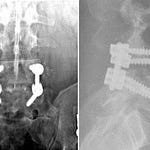

Carrying the head too far forward in a fixed posture in front of the line of gravity, common to people spending all day on their computer, generates enormous compressive forces where the neck joins the thorax (cervico-thoracic junction). Pain referral patterns from strain here can mimic a heart attack.

. . . with pain referred to the front of the chest